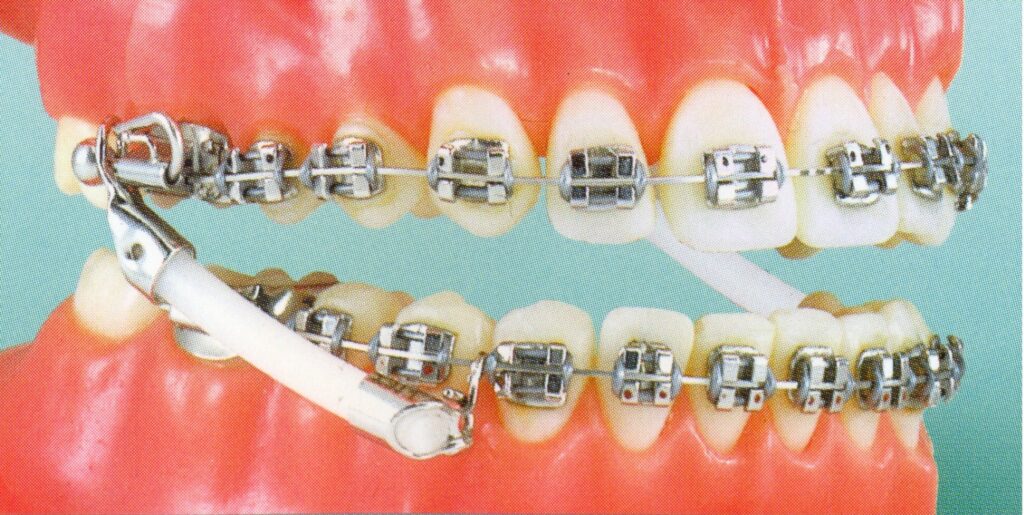

Abb. 18: Jasper Jumper [Dr. Nessler]

Im Wesentlichen sind dies elegante kleine Federkonstruktionen, die an festsitzenden oder auch herausnehmbaren Spangen das Zusammenbeißen regulieren können.